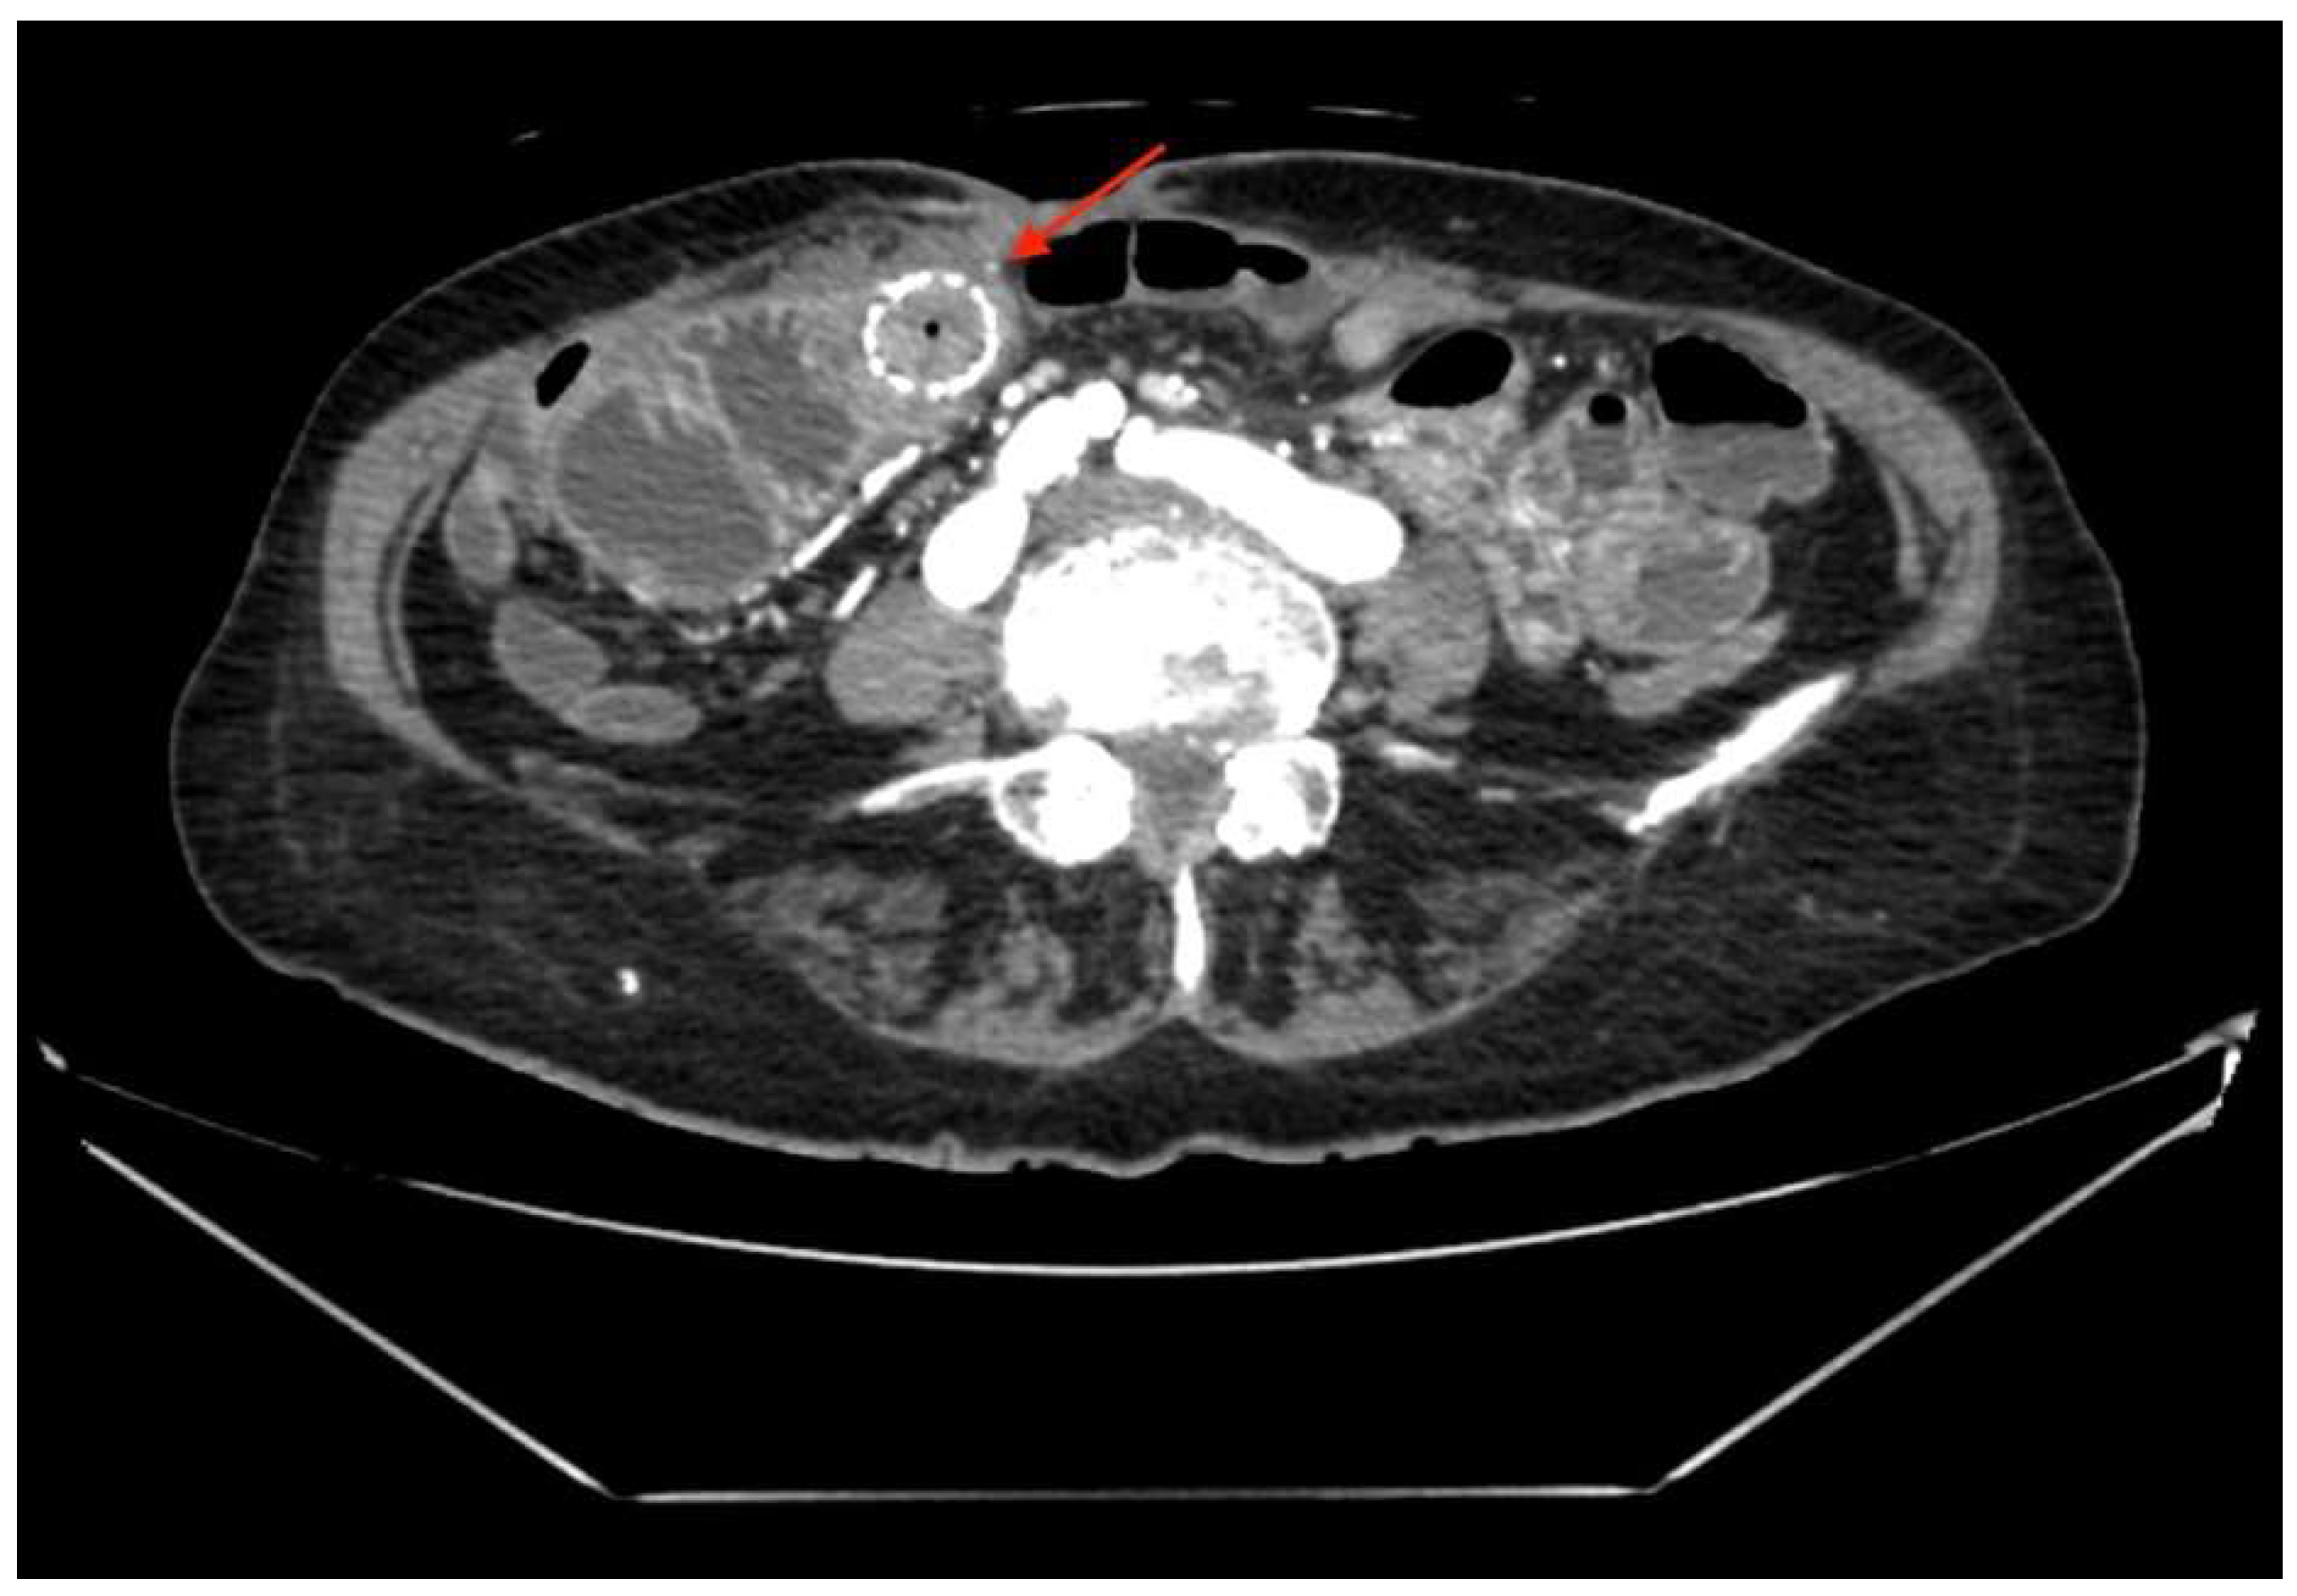

A 75-year-old woman presented to the ER with right upper quadrant pain, nausea, and vomiting due to acute cholecystitis. The history was significant for an open right hemicolectomy that was performed 6 years before this admission due to colon adenocarcinoma. Threee days after the laparoscopic cholecystectomy, the inflammation markers were found to be elevated (WBC 11.36 × 109/L, CRP 213 mg/L) and a diffuse peritonitis was identified. That same day, an exploratory laparotomy was performed. During the surgery, the small bowel was found to be perforated from suspected thermal injury (about 80 cm from plica duodenojejunalis), which was reconstructed successfully by primary bowel suture. Seven days after the surgery, a small intestinal eventration with a renewed bowel perforation was identified and a conservative treatment was initiated. Despite conservative treatment, the small intestinal fistula increased and eventually its ends separated, resulting in two open intestinal lobes. More than a month after the total parenteral feeding was initiated, the HANAROSTENT TLD-20110-230 (a single-use duodenal pyloric partially covered self-expanding metal stent) was inserted at both ends of the small intestine and fixed with single sutures to restore intestinal integrity. Two weeks after the implantation, the bowel fistula reoccurred; however, the output was noted to be comparably lower. The metallic stent was left in place for a longer time despite manufacturer’s recommendations, to act as a metal carcass to facilitate the healing of the external fistula. Seven months later, the patient was discharged after the total closure of the fistula (verified by upper GI and small bowel series), while being able to tolerate a regular feeding regimen. The follow-up appointment was scheduled to remove the stent, but unfortunately, the patient did not show up for the appointment. For the following 2 years, the patient was being intermittently hospitalized to a different hospital, due to mechanical bowel obstructions, which were treated conservatively due to the patient refusing surgery. Two years after the initial discharge from the primary hospital, the patient was admitted into our care due to acute bowel obstruction. The metabolic panel showed signs of chronic malnutrition with significant hypoproteinemia (29.7 g/L) and hypoalbuminemia (56.7 g/L), with a BMI of 20.76 kg/m2. Abdominal CT (Figure 1) showed a small bowel stent with fibrous/tumor-like changes around it (signs of small bowel obstruction).

Figure 1. A small bowel stent with fibrous/tumor-like changes around it (red arrow).